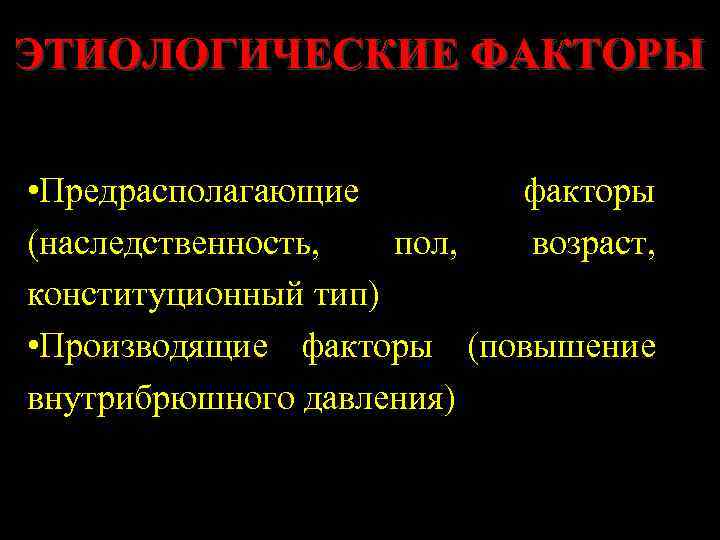

ЭТИОЛОГИЧЕСКИЕ ФАКТОРЫ • Предрасполагающие факторы (наследственность, пол, возраст, конституционный тип) • Производящие факторы (повышение внутрибрюшного давления)